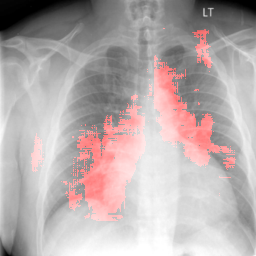

4.2 Localization

For any diagnostic task, it is desirable to gain intuitive understanding of why a certain classification decision is made rather than being a black box method. In other words, it is desirable to distinguish features that contributed most to certain abnormality in the entire chest X-Ray. There are various ways of achieving this goal [25, 30, 31, 32]. The method used in [25] is the simplest, where a patch is occluded in the image to measure its impact on the eventual classification confidence score. We have used this method to find the regions in the image responsible for a certain abnormality detection. As a representative example, we have used cardiomegaly and pulmonary edema which occur in heart and lung areas respectively. The localization scheme described in section 3.4 is followed with a patch size of pixels taking lowest values of probabilities. Instead of gray level occlusion as in [25] we found that black level occlusion works better for CXRs. This is due to the fact that the CXRs themselves are mostly gray level and occlusion of the same level does not hide much information compared to the neighborhood.

4.2.2 Pulmonary Edema Localization

In order to test the effectiveness of the localization procedure in areas other than the heart region, we chose pulmonary edema which occurs in the lung region. Also, pulmonary edema is detected by the net like white structure in the lung area. No anatomical shape change is associated with the abnormality. We have found that the localization is obtained best when the ROIs of lungs are taken to compute the map. Following the scheme in section 3.4, localization experiment on pulmonary edema is performed as shown in Fig. 8. It has been observed that the classifier is not sensitive to the fine features like septal or Kerley B lines. The localization is mainly obtained in the lung region where excess fluid is observed. Some localization regions are outside the lung region which occurs primarily for the fact that, even though the occlusion center is outside the lung, it occludes lung region and thus the probability drop occurs.

8 Additional Examples of Localization

In this section we show more examples of localization. Few localization samples are shown in Fig. 11. It can be observed that, in the CXRs with Cardiomegaly (Fig. 11(a) and (b)) a fine localization around the heart is observed. In the normal CXRs (Fig. 11(c) and (d)) such localization is not observed. Rather the lowest probabilities are spread out in the CXR image. It is interesting to note that, the localization algorithm gets low probability where the heart is enlarged during cardiomegaly, but the proportion is small compared to the localization in other areas of normal CXRs. In order to observe the performance of the heat map we computed histograms of heat maps of each of the 100 CXRs in the test set for Cardiomegaly detection and average histograms are shown in Fig. 11(e) and (f) for CXRs with Cardiomegaly and normal CXRs, respectively. It is to be noted that, the histograms include both success and failure cases. It can be observed that, for CXRs with Cardiomegaly the classifier is highly sensitive toward Cardiomegaly detection even under occlusion. This indicates that, the classifier primarily looks for local features in a CXR instead of some feature that is spread out in the entire CXR. However, the classifier is not sensitive toward normal CXRs under occlusion. Rather, the probabilities are spread out in the probability spectrum. After that, we analyzed the failure cases where the classifier is unable to classify the image correctly. Two such examples of failure cases are shown in Fig. 12. The localized CXR shown in Fig. 12(a) contains Cardiomegaly whereas the classifier detects it as normal. However, the localization shows that it localizes around heart quite well despite the in accurate classification. On the other hand, Fig. 12(b) shows an example of normal image which has been classified as Cardiomegaly by the classifier. There is stronger localization around the hear that that is observed for normal images as in Fig. 11(c) and (d), however, like those images the localization is spread out.

In a similar fashion, additional localization results for Pulmonary Edema is shown in Fig. 13. In Fig. 13(a) and (b) localization of two examples of CXRs with Pulmonary Edema is shown. As stated earlier the classifier localizes in the lung region. This is not the case when normal images are used to localize Pulmonary Edema as seen in Fig. 13(c) and (d). The localizations are obtained in random dense locations such as the sternum or heart. Like the cardiomegaly case, the histogram averages for CXRs with pulmonary Edema (Fig. 13(e)) shows a sensitivity toward pulmonary edema detection while the normal CXRs shows a spread out detection. It is interesting to note that, in the histogram of normal images high probability (¿0.85) is non-existent, thus ensuring low false positive rate. In the test set none of the normal images have been diagnosed as Pulmonary Edema. The failure cases are shown in Fig. 12. These CXRs are with Pulmonary Edema. However, the localization algorithm shows that one of them localizes in lungs whereas the other one shows a localization pattern similar to that obtained in normal CXRs.